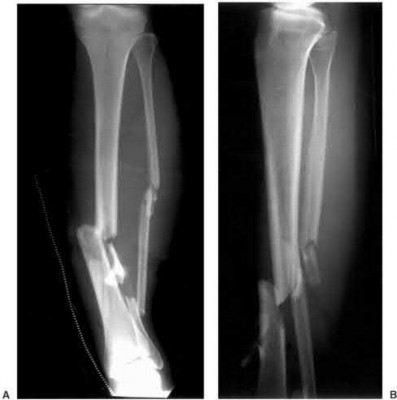

Question 19

A 28-year-old male sustains a closed comminuted tibial shaft fracture.

Two hours post-injury, he develops severe leg pain unyielding to narcotics. His blood pressure is 120/80 mmHg. Intracompartmental pressure monitoring is performed. Based on current guidelines, which measurement dictates an emergent 4-compartment fasciotomy?

Explanation

Acute compartment syndrome is classically defined by tissue hypoperfusion. The absolute compartment pressure is less reliable than the differential pressure (Delta P). A Delta P (Diastolic Blood Pressure minus Compartment Pressure) of less than 30 mmHg is an absolute indication for emergency fasciotomy, as capillary perfusion gradient is lost when tissue pressure approaches the diastolic pressure.